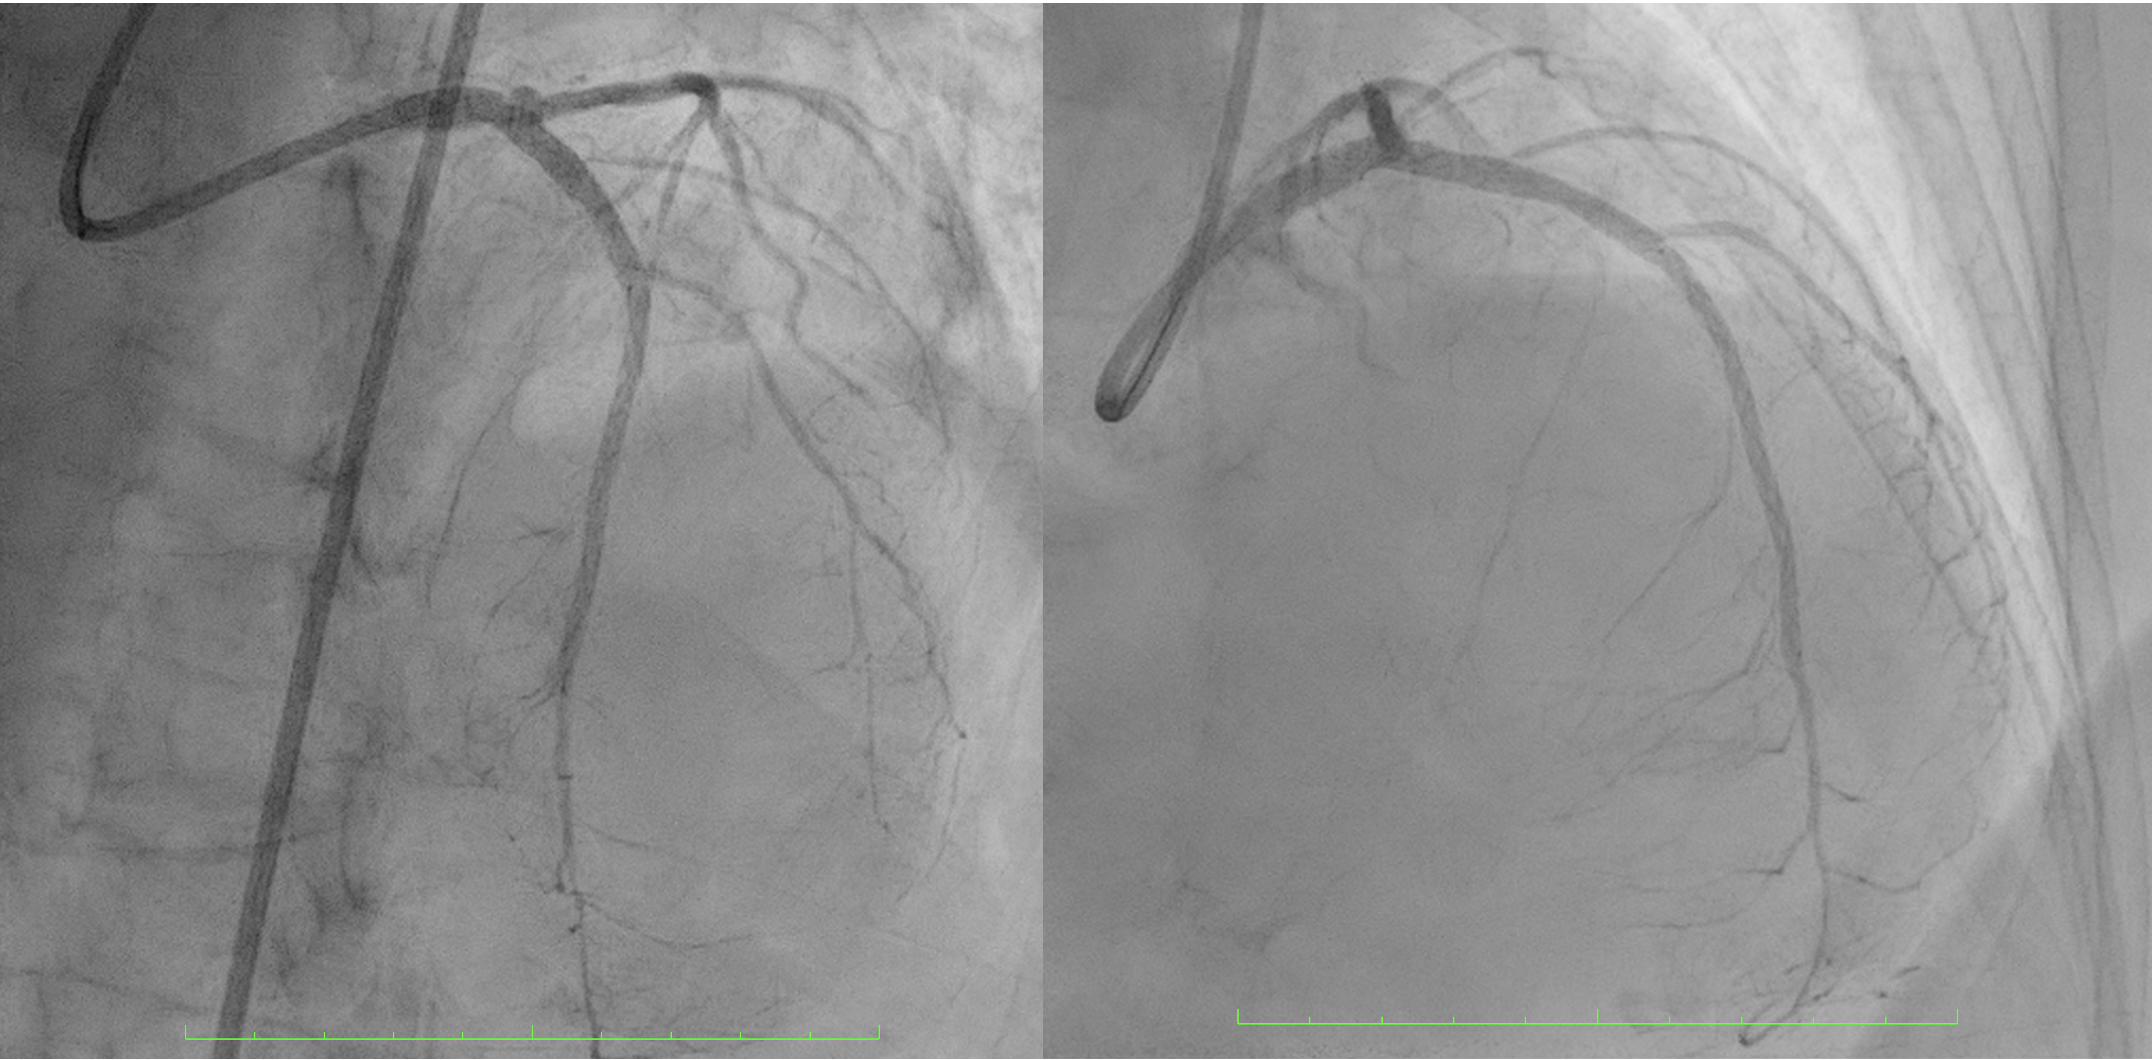

Angiography showed 80% stenosis in the distal LM, with diffuse disease in LAD and a maximum 85% stenosis in the mid-LAD. There was a moderately calcified lesion extending from the distal LM to the proximal LAD. The LCx was normal, and the RCA had a 50% ostial stenosis. An IVUS catheter was advanced over a floppy wire showed a 270¡Æ calcified arc, 4 mm in length from the distal LM to the ostial LAD. The MLA of LM, osteal LAD and distal LAD consecutively was 3.25 mm©÷, 3.2 mm©÷ and 2.37 mm©÷

Based on angiographic and IVUS findings, the lesion was prepared using a scoring non-compliant (NC) balloon (ScoreFlex) 2.5 mm ¡¿ 15 mm, inflated from the distal LAD to distal LM at a maximum of 18 atm. A first drug-eluting stent (DES) Cre8 2.75 mm ¡¿ 46 mm was deployed from the proximal to distal LAD, followed by a second DES (Combo Plus) 3.5 mm¡¿ 38 mm from the distal LM to the proximal LAD with overlap. During withdrawal of the stent balloon, the guiding catheter (XB 3.5/ 7 Fr) advanced too deeply, resulting in crushing of the proximal portion of the Combo Plus stent. Angiography showed that the crushed stent no longer adequately covered the distal LM lesion. Attempts were made to reopen the crushed segment using a series of semi-compliant balloons (Sapphire II Pro): 0.85 mm ¡¿ 15 mm, 1.0 mm ¡¿ 15 mm, and 2.0 mm ¡¿ 15 mm, each inflated to a maximum 20 atm. A non-compliant (NC) balloon 4.5 mm ¡¿ 8 mm was then used to dilate the stent struts. A third DES (Ultimaster Tansei) 3.5 x 24 mm was deployed from the ostial LM to the proximal LAD, overlapping the previously crushed stent. Proximal optimization (POT) was performed in the LM using a 4.5 mm ¡¿ 8 mm NC balloon inflated to 22 atm. Final angiography showed a satisfactory result with minimal residual stenosis in the distal LM. The final IVUS assessment could not be perfromed due to damage to the IVUS catheter